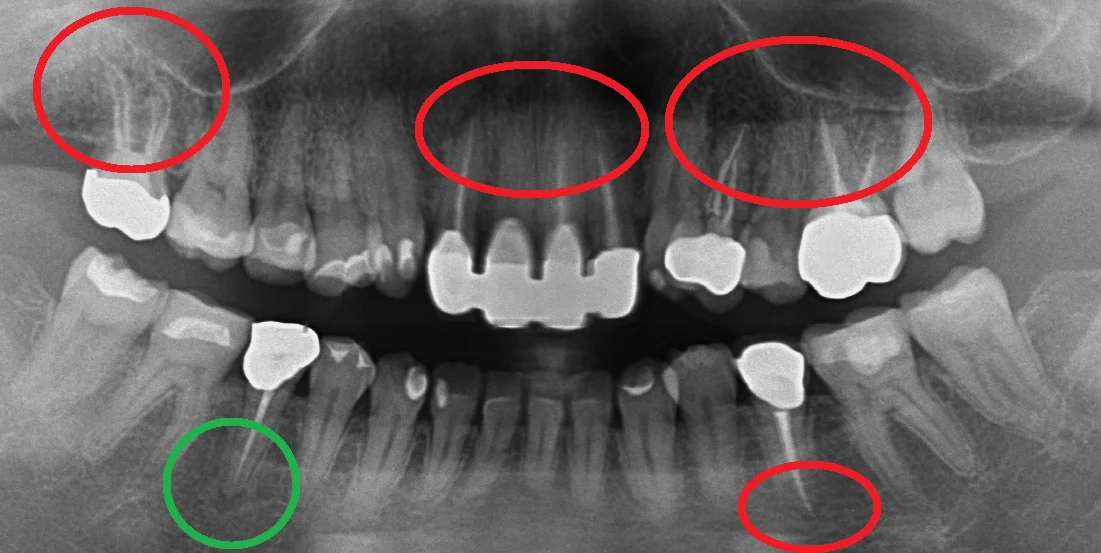

では本題の写真がこちらです。

こちらが術前で

こちらが術後1年半経過後、初診に戻った際に撮影したものです。

赤丸の部分がすべて私の方で神経の治療を行わせていただいた部分になります。

緑丸の部分が治療を行っていないところですね。

そしてそれら全てで根の先の膿が小さくなっているのがわかります。

本数的に言うと・・・7本ですね。

また治療後の補綴物も全て適合よく入っているので、まったく問題ありません。